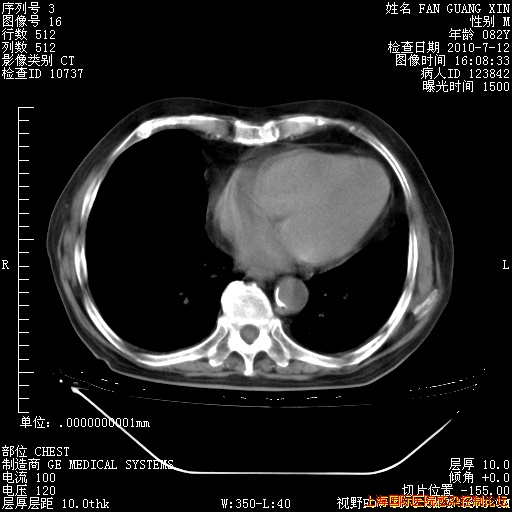

6月12日纵膈窗

今天复查CT

今天CT

整整相隔30天的肺部CT好像有所好转啊。甲强龙减量第3天,需要观察体温。

海管,自昨日你和我通完话后,不知您岳父消化道症状有无缓解?体温怎样?阅读7.12日胸部ct,个人认为目前激素治疗是有效的,甲强龙减量是适宜的。因在抗痨治疗,需密切观察肝功、肾功能和血常规。不过,老年、长期住院和大量使用激素,很担心菌群失调发生